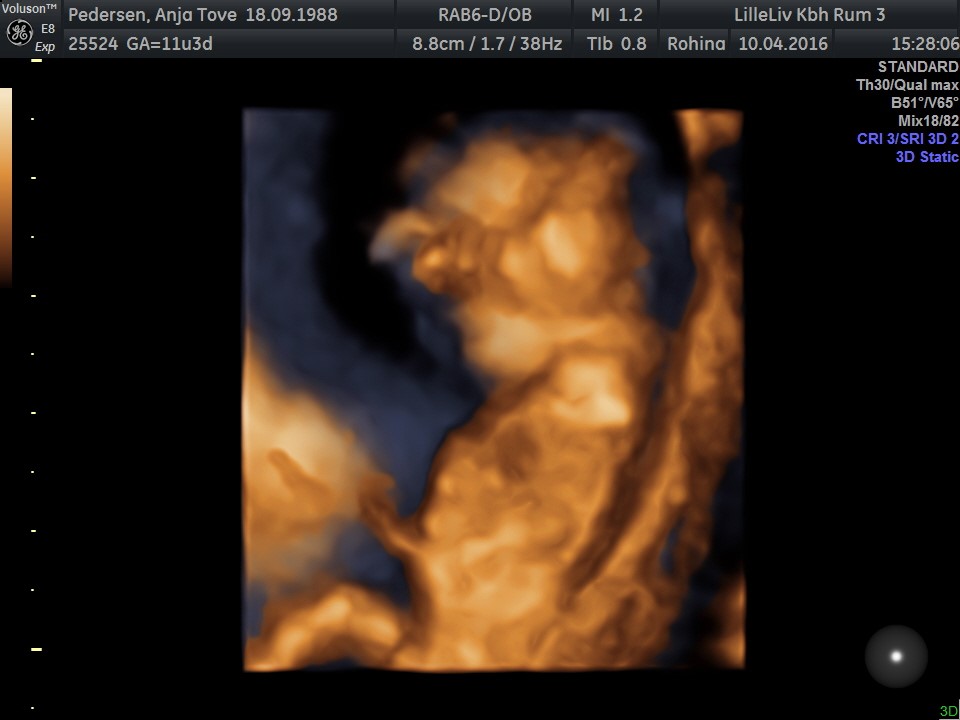

Der var meget lang ventetid så vi fik lige lov til at se i 3D og 4D selvom vi ikke havde betalt for det - så fantastisk en oplevelse!

Hun behøvede slet ikke at lede efter hjertet, for den hoppede lystigt rundt derinde. Og hver gang hun satte 4D til for at se bevægelser så lå den stille, en rigtig bølle

Ansigtet skulle vi så heller ikke se for arme og hænder lå konstant oppe ved hovedet